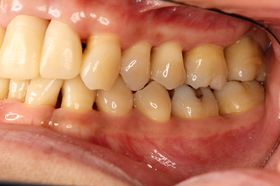

下の写真は、中等度~重度の歯周病に罹患した患者さんの初診時写真です。

全顎的にプラークや歯肉縁上・縁下歯石の付着が著明で、歯肉の炎症もとても強い状態でした。

上顎の前歯や一部の奥歯はかなり動揺(グラグラする)していました。